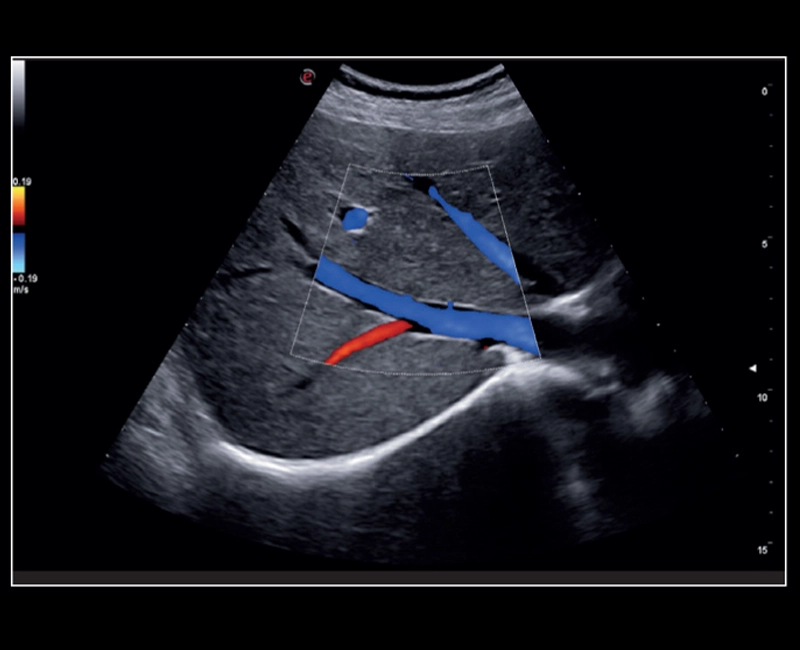

Q7 - Cardio CFM

Q7 - Cardio CFM